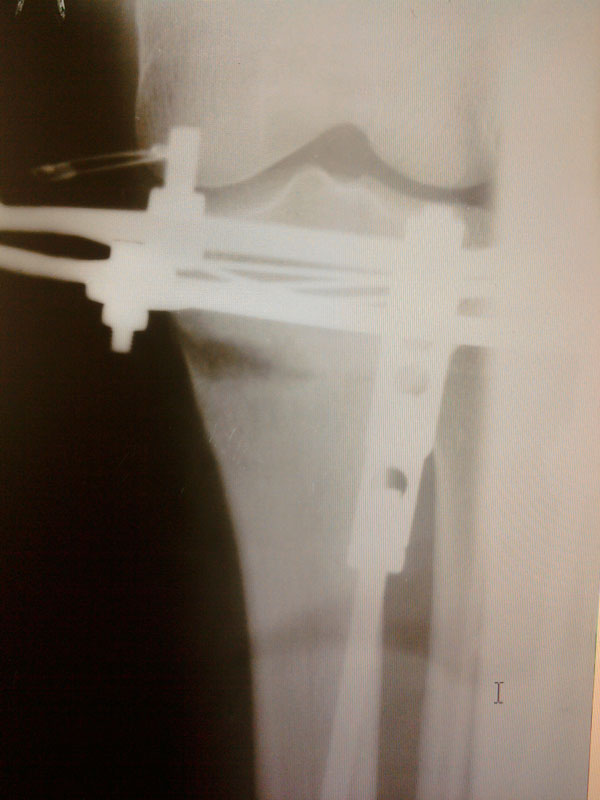

Здравствуйте, Николай Николаевич! Посмотрите мои снимки, пожалуйста - когда мне приезжать?

Здравствуйте, Марина! Судя по рентгеновским снимкам, регенерат(костная мозоль) у Вас замечательный. Чтобы не испытывать судьбу, учитывая всё таки выраженную деформацию ног, оптимальное снятие аппаратов(чтобы сразу ходить без костылей и других средств опоры) 20 марта. Осталось чуть- чуть потерпеть.

До встречи, удачи!